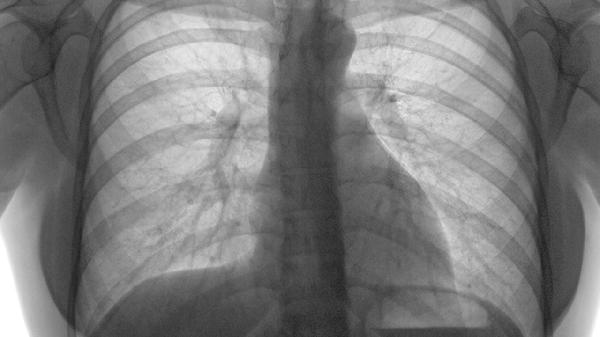

胸部放疗后出现的咳嗽、咽痛等放射性肺炎症状,可在医生指导下使用养阴清肺膏辅助治疗。其滋阴润肺特性有助于减轻放射线对呼吸道的损伤,使用期间需监测肺部影像学变化。